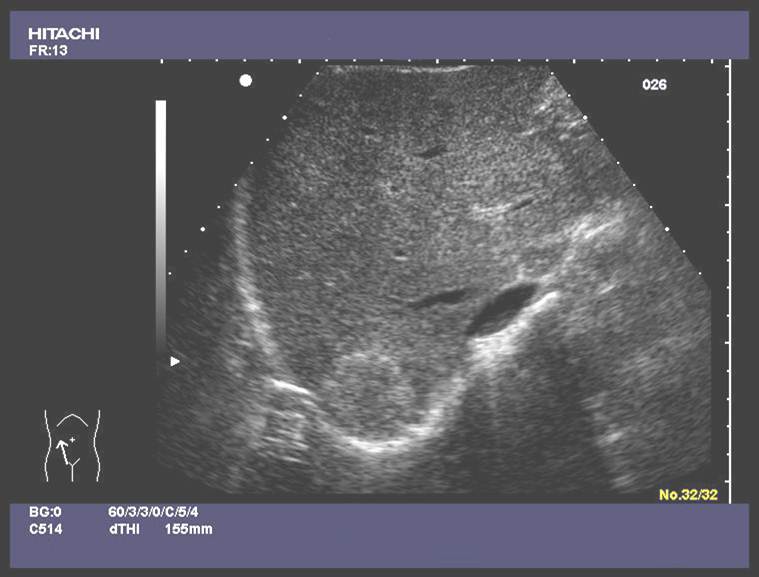

SONO

Not advanced: hyperechoic, enlargment, decreased vasculature

ENd stage small noduar, ascites suround